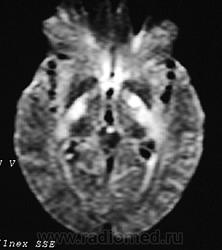

ГМ. Рассеянный склероз 2. +

Рассеянный склероз